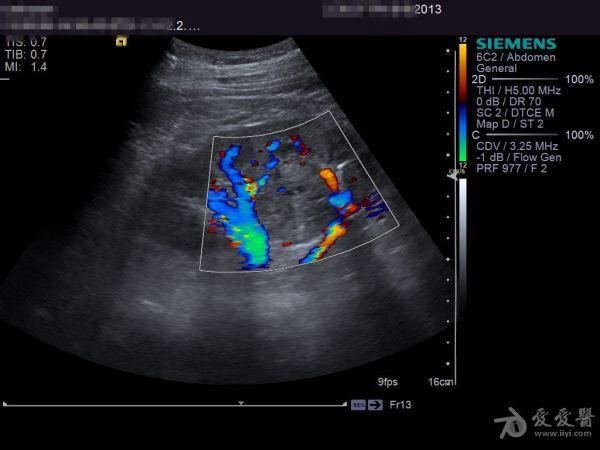

肾肿瘤彩超

肾肿瘤彩超,肾肿瘤ct